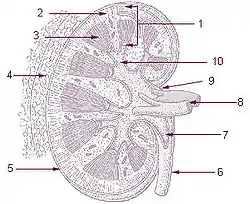

- The renal cortex, between the renal capsule and the renal medulla; assists in ultrafiltration